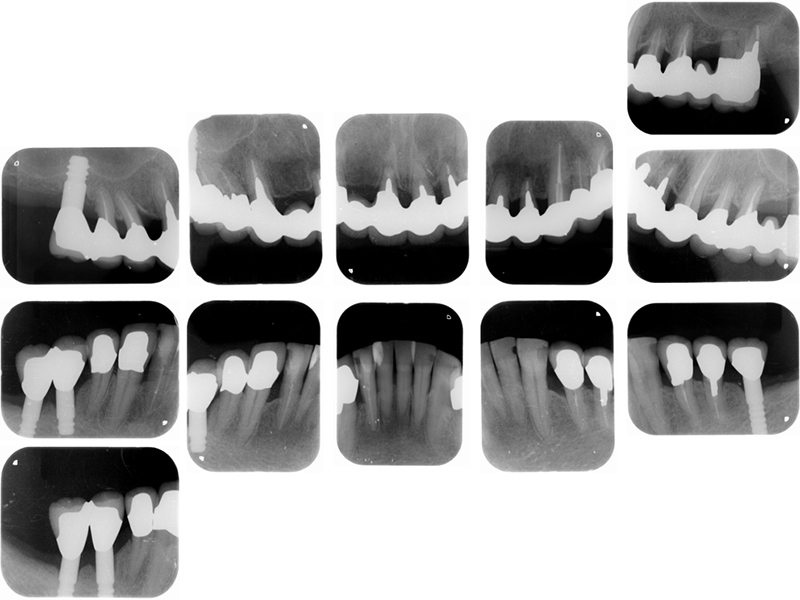

治療前X線写真